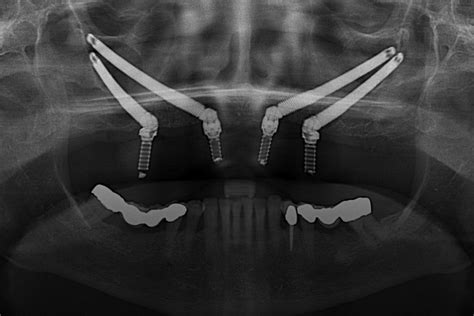

- Implantes transcigomáticos: Esta técnica consiste en la inserción de un implante en la región palatina del segundo premolar, de entre 35 y 55 mm de largo, que tras un recorrido intrasinusal es anclado al hueso cigomático.

Colocación de implantes cigomáticos en el maxilar superior.